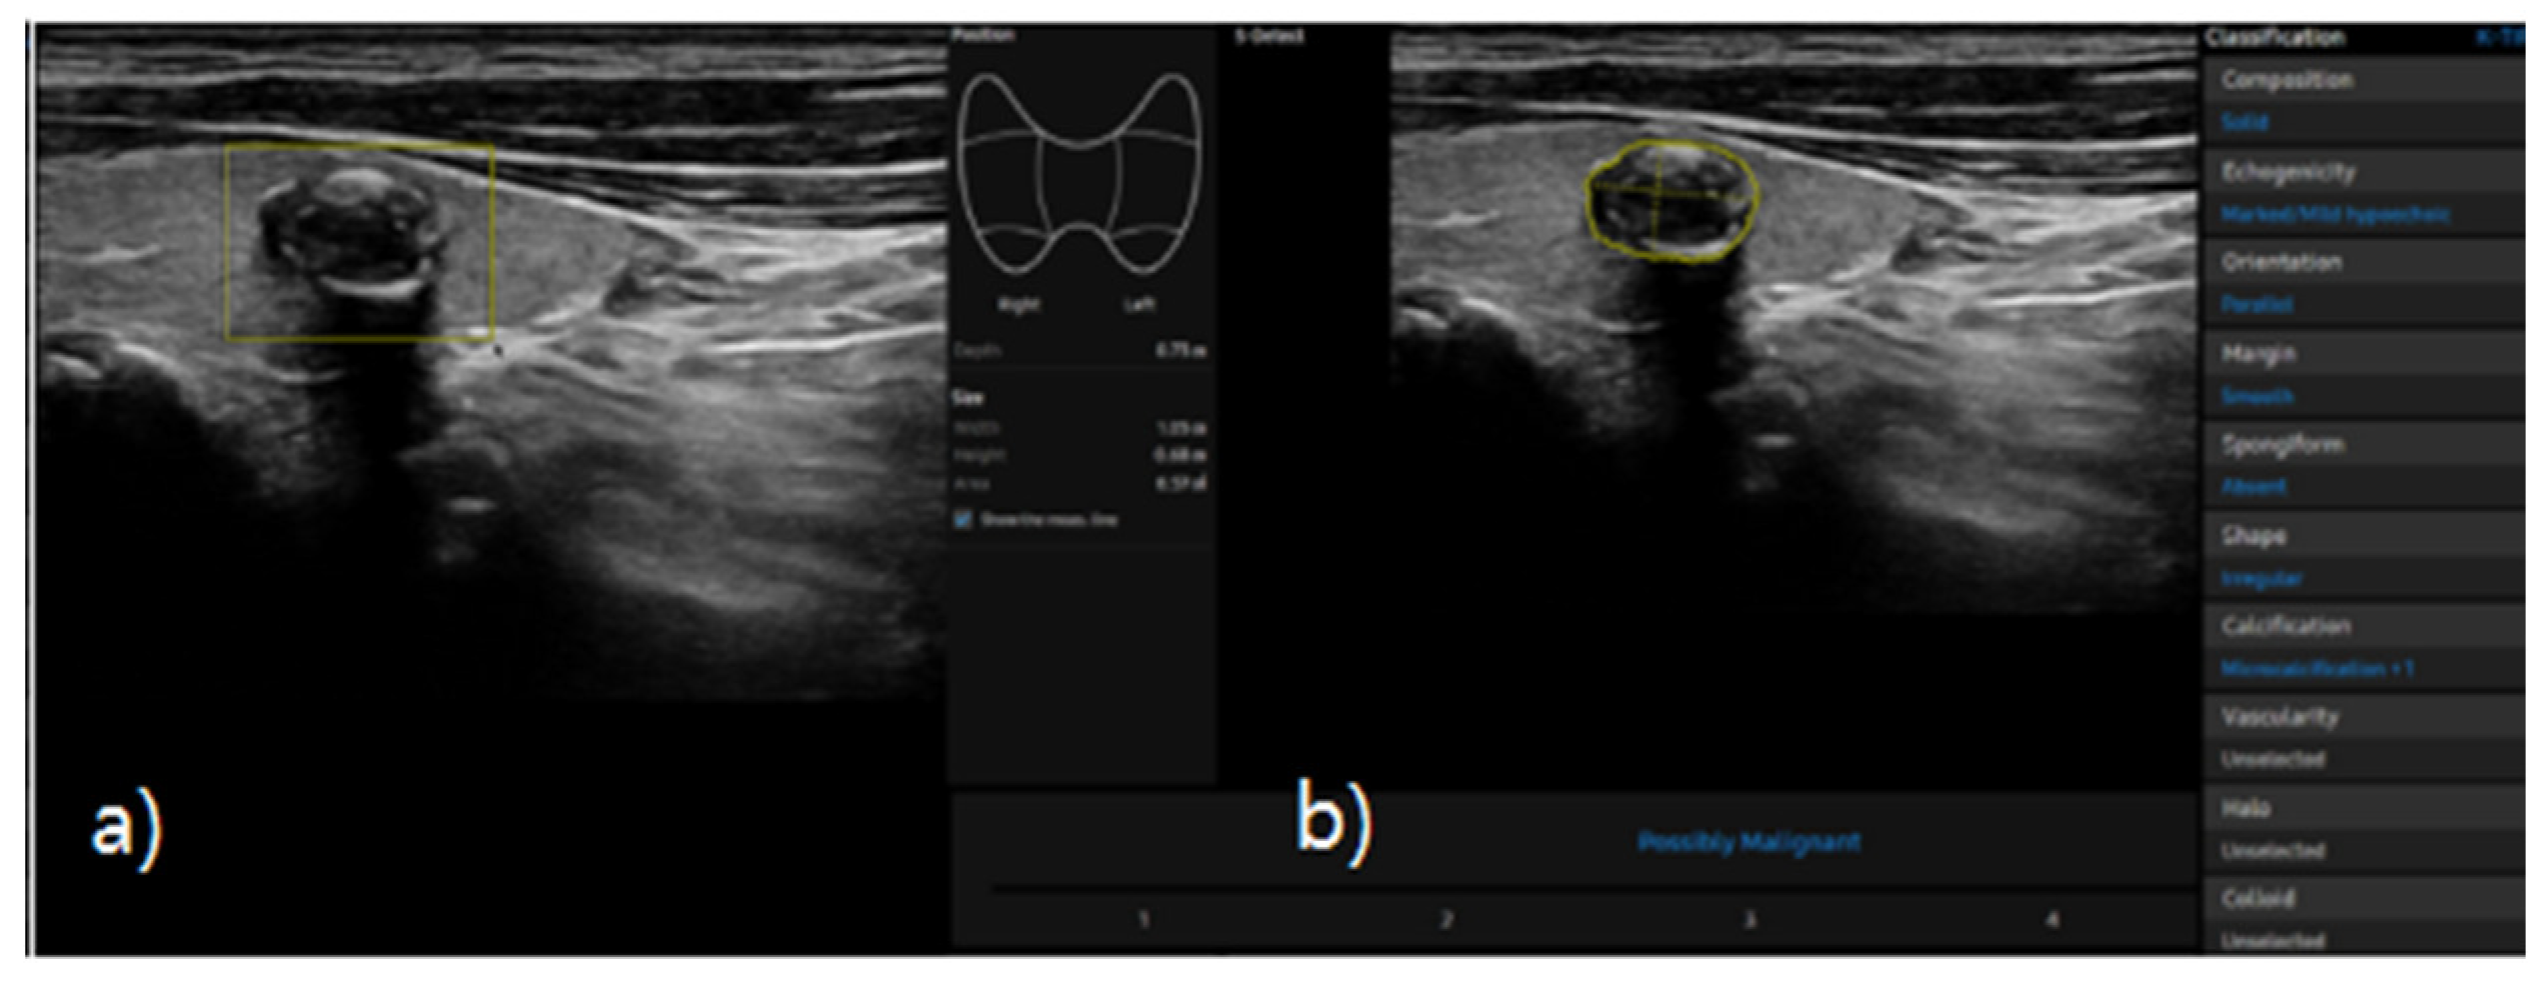

S-detect is an AI-based CAD software designed for ultrasound image analysis. Upon establishing the region of interest (ROI) for the targeted nodule, the software automatically delineates the boundaries and initiates the analysis [21,25]. If there errors the boundaries delineated by the software, manual delineation of the boundaries was performed. First of all, conventional ultrasound scanning was performed. After freezing of a static ultrasound image of the thyroid nodule, the ROI was manually set around the lesion, and S-detect was subsequently utilized to analyze the lesions. The nodules were then classified as “possibly benign” or “possibly malignant” based on characteristics such as internal composition, echogenicity, orientation, margin, and shape. All classifications rendered by S-detect (“possibly benign” or “possibly malignant”) were independently reviewed by an internal medicine specialist with over 20 years of experience in thyroid imaging. This procedure is depicted in Figure 3 and Figure 4.

Figure 4. a) Ultrasound grayscale longitudinal image of the left thyroid lobe in a 69-year-old man. b) Thyroid nodules automatically classified as “possible malignant” using S-detect according to characteristics such as internal composition, echogenicity, orientation, margin, and shape.